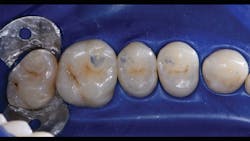

The final piece of the puzzle is the composite materials. In this case, Filtek One Bulk Fill Restorative (3M) and Filtek Bulk Fill Flowable Restorative (3M) were used. Bulk filling is more time efficient, technically simpler, and creates a monolithic form. Manipulation of composites and layering is known for a higher incidence of voids and defects. This case demonstrates the method of injection molding, which has the ability to create strong, monolithic, void-free, ideally contoured, mirror-finish restorations. Significant time savings occurs with simpler finishing requirements. Excess composite at the mid buccal, lingual, and occlusal areas is quickly reshaped with a disc. The subgingival area is then finished with a finishing strip. Finally, it’s time to finish and polish using a diamond-impregnated rubber polisher.

Just as Tofflemire bands, wooden wedges, and amalgam were suited for one another, anatomic matrices, wedges, separators, and flowable and bulk fill composites work harmoniously to create ideal posterior composite restorations that are strong, monolithic, and anatomic.

In the following case study (figures 1–11), the techniques and methods discussed will be demonstrated with the treatment of a quadrant of four posterior restorations. Four interproximal smooth-surface carious lesions are conservatively treated with two nonretentive saucer preparations and two marginal ridge-preserving opportunistic preparations.